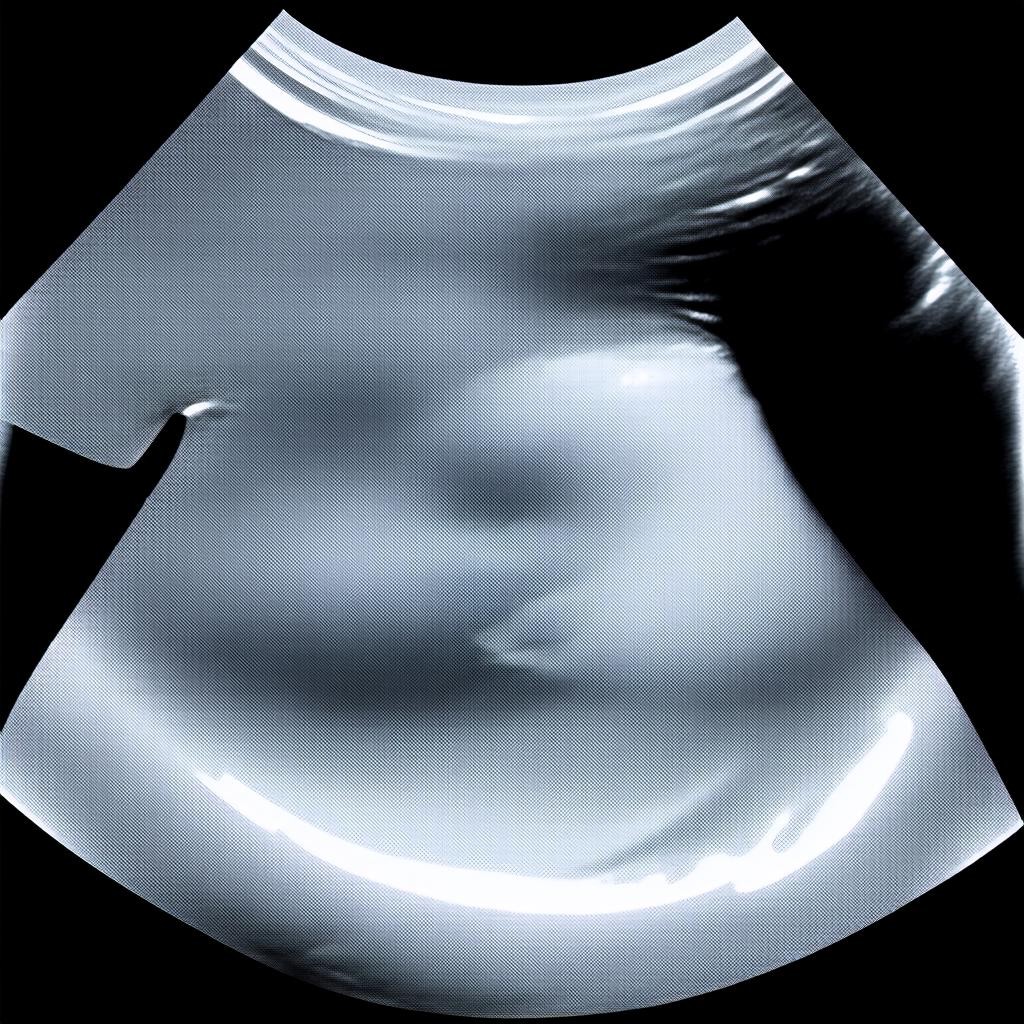

15 неделя беременности — важный этап, когда будущая мама может пройти плановое ультразвуковое исследование (УЗИ). На этом сроке врач оценивает развитие плода, проверяет соответствие нормативам и, при благоприятных условиях, может определить пол ребенка. УЗИ на 15 неделе проводится трансабдоминально (через живот) и является безопасным для малыша и матери.

К 15 неделе плод активно растет и развивается. Его размер составляет около 10-12 см, а вес — примерно 50-70 грамм. Основные изменения в развитии включают: